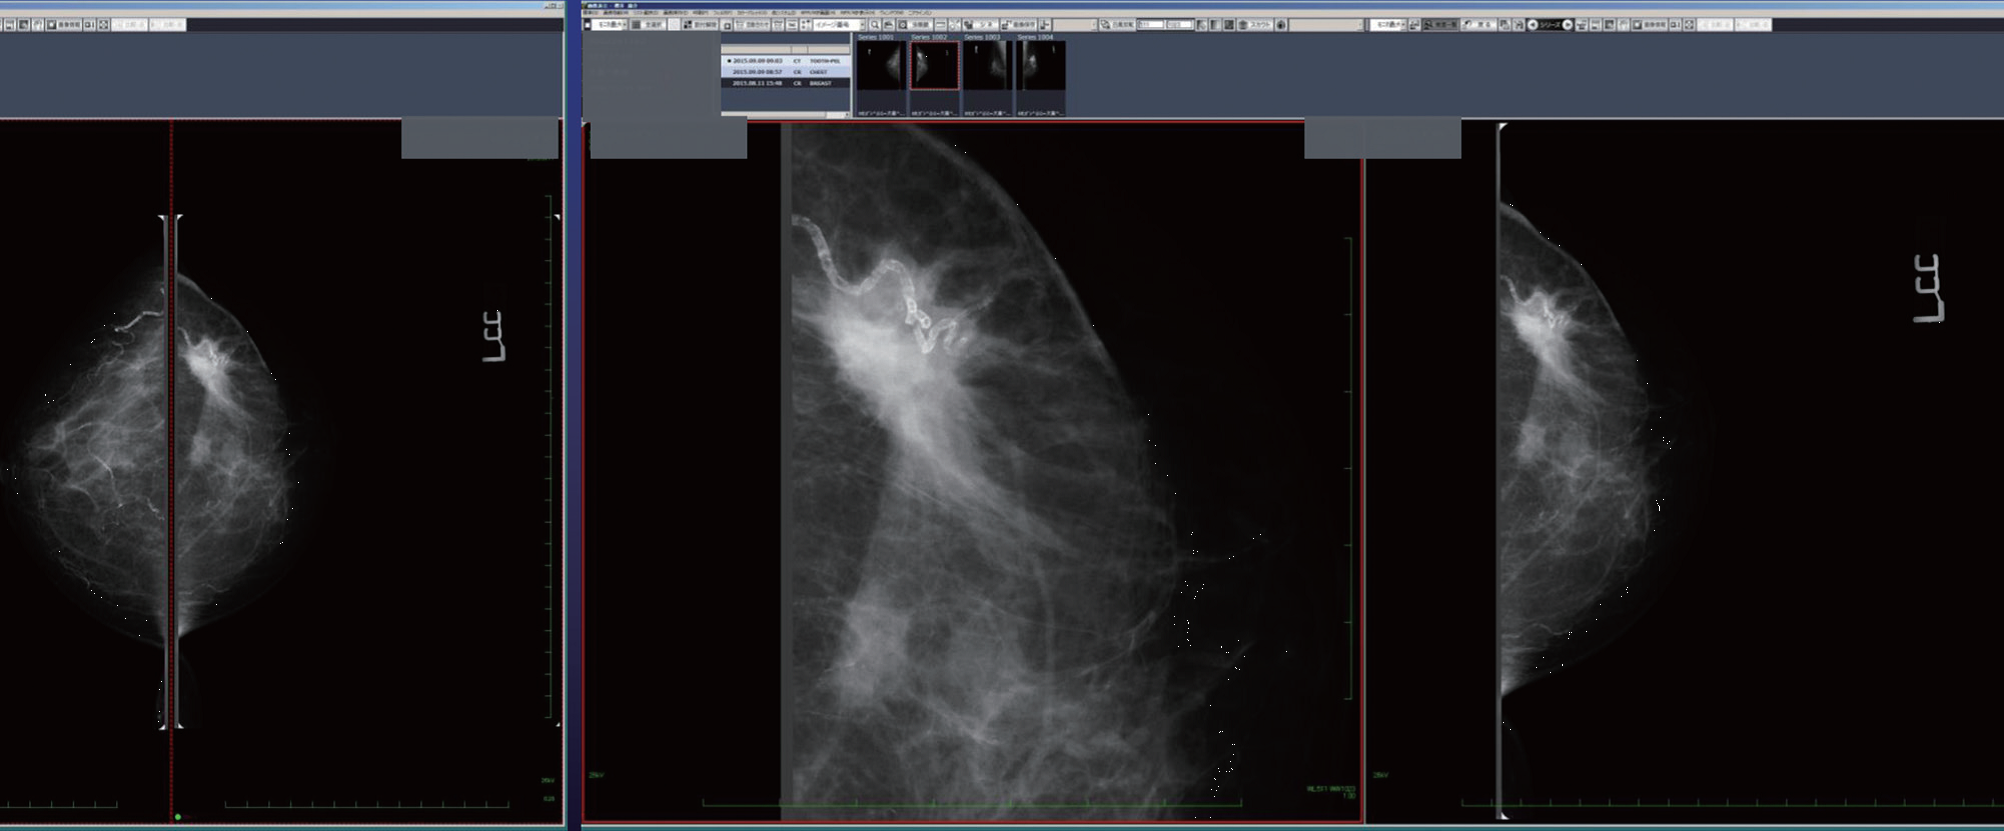

4Kモニタによるマンモグラフィ診断

読影では、まず4分割モードで、MLO(内外斜位方向)とCC(頭尾方向)の感じをざっとつかむ。次に、前回比較モードを選ぶと、前回と今回のMLO、前回と今回のCCという具合に対比ができる。

この状態からピクセル等倍モードに移行して見る。なぜなら、全体画像表示や4分割の全体画像表示ではほとんどの石灰化が検出可能であるが、ごく一部の微細石灰化は検出困難だからである。ピクセル等倍モードにして初めて認識できる。したがって、全体表示だけでスクリーニングを終わらせることは残念ながらできない。ピクセル等倍では、乳腺全体を完全にカバーすることはできないが、3分の1から2分の1ぐらいを一度に表示することは可能だ。この状態で画像を左右に動かすことで、ほぼ全体をピクセル等倍で観察することができる(図2)。

ピクセル等倍で足りない場合、虫眼鏡モードで拡大する。今後Retinaディスプレイが普及してくると、ソフトの充実も必要で、ワンタッチで200%、あるいは400%拡大といったモードが必要になってくるだろう。

乳腺全体のほぼ3分の1~2分の1まで表示可能だ。

結論としては、4Kモニタによるマンモグラフィの診断は、4分割モード、比較モード、等倍モードのような読影フローを工夫することで、十分実用に耐えるといえる。モニタサイズについては、机に置く大きさとしては37インチが限界だと考える。また診断上、視野の中に占める画像サイズが極めて重要になり、モニタは大きすぎても小さすぎてもだめなので、観察距離や画像サイズで調整すればよいといえる。